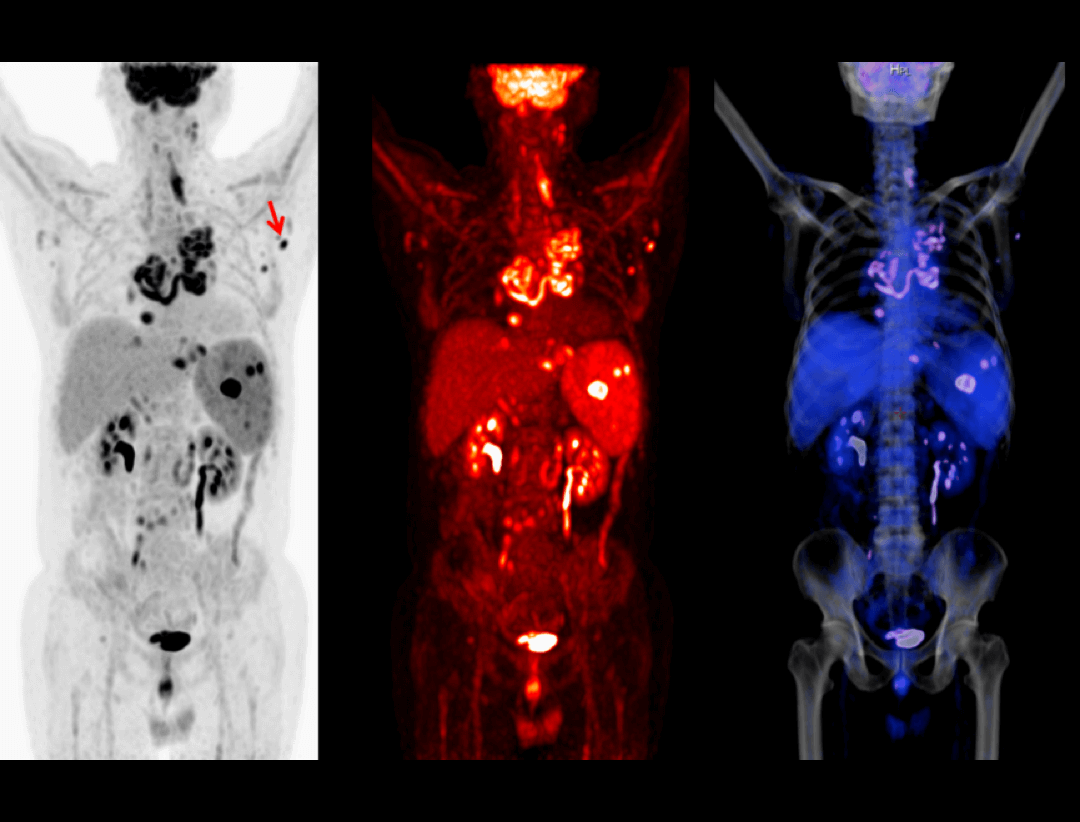

The very fine sampling voxels acquire massive information, bringing exquisite visualization of fine anatomic details.